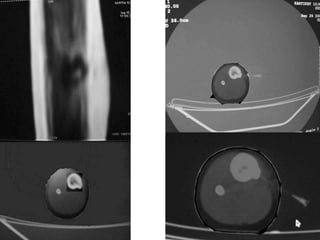

Osteoid Osteoma - CT

• CT is more accurate than MRI.

• CT helped in confirming the diagnosis of

osteoid osteoma in 74% of cases.

• Szendroi et al reported accuracies of about

66% in the diagnosis of intra-articular lesions

and 90% in extra-articular lesions.

• To date, CT scanning is the primary

investigational tool for the definitive diagnosis

of osteoid osteoma.

• A CT guided needle was passed to localize the

lesion.

• Through an anterior "Hernia" approach the

lesion was approached and excised.

• The Follow-up CT Scanning done to reveal

complete removal of lesion.

• A biopsy confirmed it later.